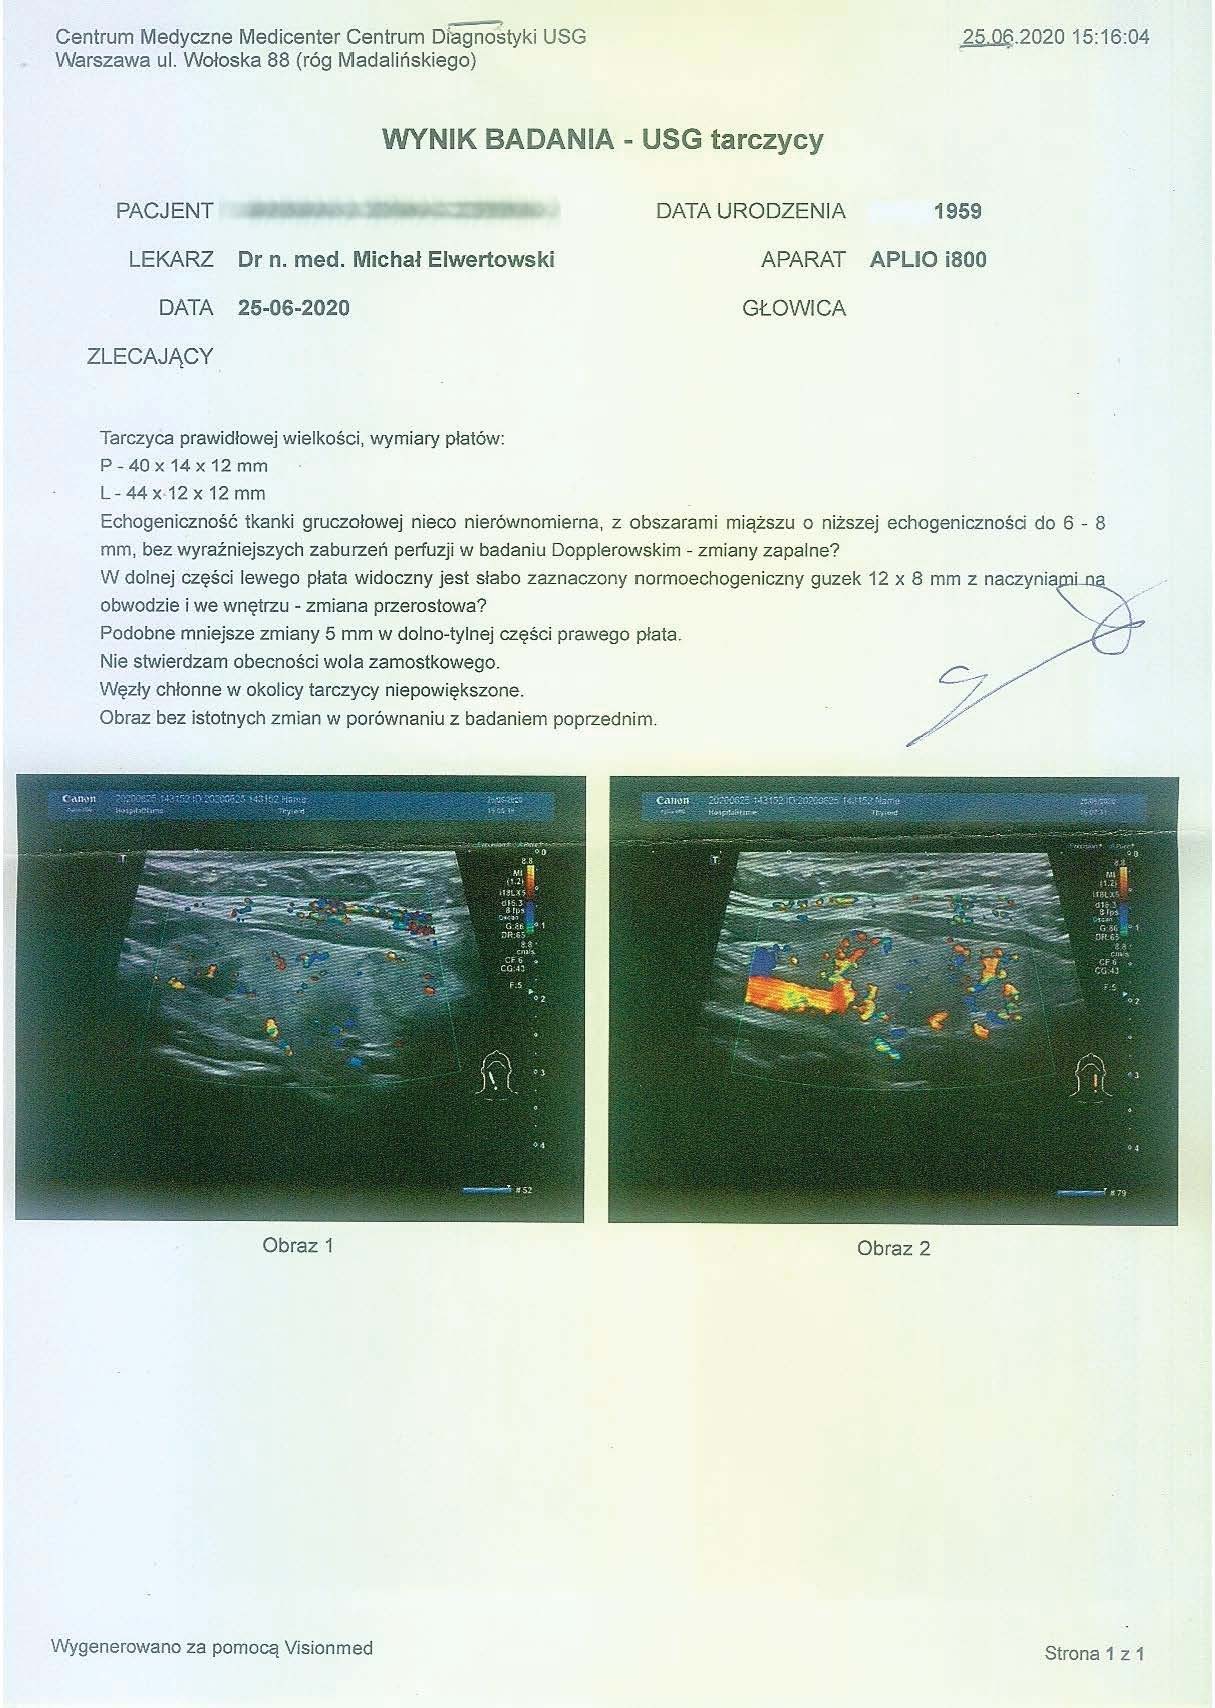

EFEKT PREPARATU PRZY GUZKACH NA TARCZYCY

Przypadek kobiety lat 46, przed podaniem preparatu wykryto guzki na tarczycy o wymiarach 9x4 mm i 5x8 mm, po zaledwie miesiącu stosowania bez dodatkowej farmakologii guzki zmniejszyły się do rozmiarów 7x4 mm i 5x3 mm. Szybka redukcja guzków (~20-65% ) bez ingerencji chirurgicznej i farmakologicznej wskazuje na naprawę komórkową na poziomie mitochondrialnym, co zapobiega nieprawidłowym podziałom komórkowym i rozwoju guzów. Preparat zwiększa wydajność mitochondriów do produkcji ATP, stymulując apoptozę uszkodzonych komórek, jednocześnie wpływając na regenerację i tworzenie poprawnych struktur. Jest to szczególnie wartościowe w przypadku guzów łagodnych, gdzie standardową procedurą jest jedynie obserwacja zmian, co najczęściej prowadzi do rozwoju znacznie trudniejszych do opanowania nieprawidłowości.

PRZYKŁAD EFEKTU PREPARATU NA NIEDOCZYNNOŚĆ TARCZYCY

Kobieta lat 59 z niedoczynnoscią tarczycy, bez przyjmowania lewotyroksyny. Kobieta przyjmowała preparat przez okres ponad 3 miesięcy. Przy zachowaniu naturalnego cyklu komórkowego i stałemu stymulowaniu mitochondriów osiągneła następujące wyniki kuracji:

Po ponad roku kuracji badania wykazały dalszy postęp wycofania autoimmunologi tarczycy, potwierdzone również badaniem USG narządu.